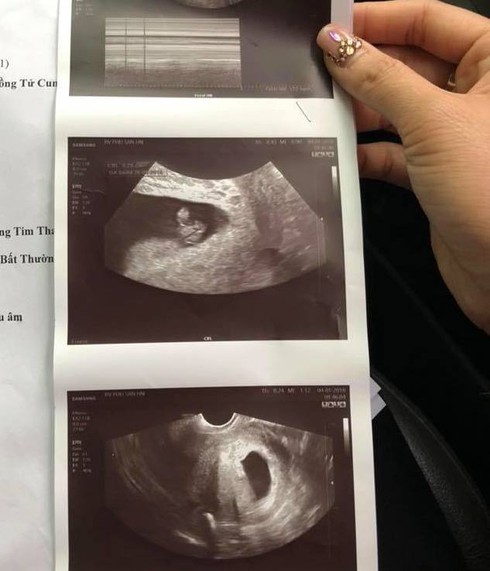

Giấy ra viện của chị M được bệnh viện Đức Giang chẩn đoán lưu thai |

Để chắc chắn về kết quả trước khi "xử lý" thai, gia đình chị M. quyết định xin chuyển viện nhưng bác sĩ vẫn khuyên "không nên". Nhưng chồng chị M. vẫn quyết định đưa vợ sang Bệnh viện Phụ sản Hà Nội để khám lại.

Trao đổi với chúng tôi, bác sĩ Nguyễn Văn Thường – Giám đốc Bệnh viện Đa khoa Đức Giang cho biết, ông đã nắm được 80% sự việc. Nhưng theo quy trình thì những người liên quan phải viết tường trình sự việc sau đó bệnh viện sẽ họp để xem xét toàn bộ quy trình. Vì ngoài nghe người bệnh nói, thì cũng phải nghe cả phía bác sĩ nói mới khách quan. Dự kiến giữa tuần sau sẽ có kết luận cuối cùng. Quan điểm của bệnh việ là “sai đến đâu xử lý đến đó”.